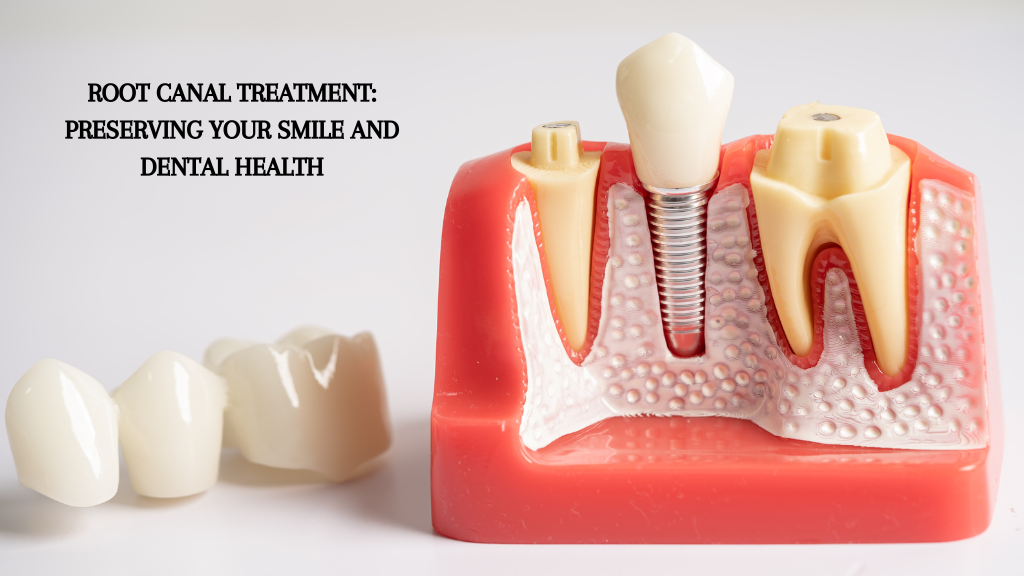

Root canal treatment is important when a tooth is severely infected or damaged. The treatment is needed if the tooth’s pulp contains soft tissue. It becomes inflamed or infected due to deep decay, postponed dental procedures, or trauma to the tooth. If the tooth...